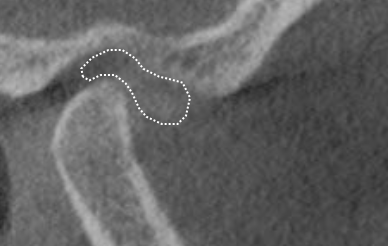

Over 40 million Americans suffer from Myofascial Pain Dysfunction (MPD), a condition that causes headaches and muscular pain. Dr. Klim uses advanced biofunctional diagnostic techniques to decrease painful tension in the head, neck, and shoulder muscles.

Many suffer from Myofascial Pain Dysfunction (MPD) and are not sure of the nature of their condition and how to solve it. You may have heard other terms that describe this condition such as TMJ or TMD. This is short for Temporomandibular Joints. Craniomandibular Dysfunction (CMD) or Temporomandibular Disorder (TMD) are another terms dentist use.